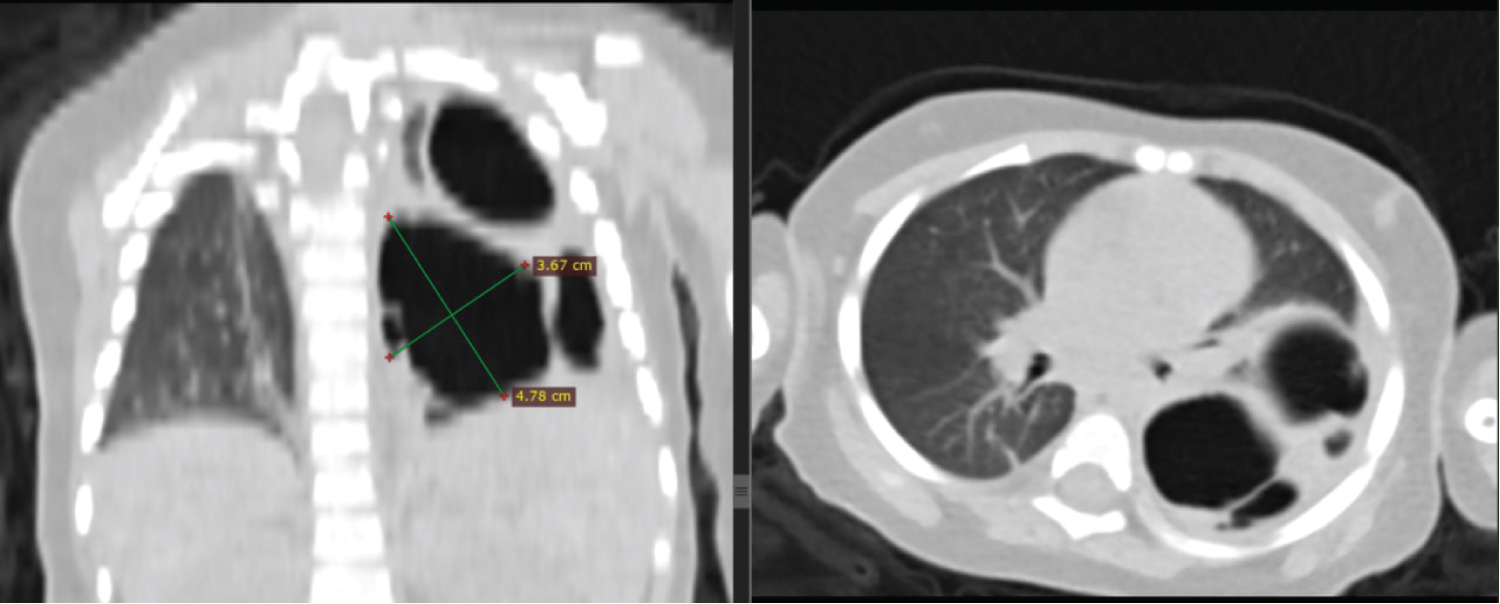

Initial non-contrast chest CT scan with 3 mm thickness revealed left side multiple cystic lucencies in mid and lower lung zone including retrocardiac location (Figure 1). The cysts were of variable sizes, and the largest cyst was 4.7 cm in diameter and was located at left lower lobe displacing the normal lung parenchyma (Figure 2). There was visible communication with the bronchial system. No soft tissue component was observed. Other mediastinal structures, pleura, and chest wall showed normal findings. There was no evidence of enlarged lymph nodes or mass lesions. The airways and fissures were well demonstrated, and no aggressive osseous lesions were seen. The final diagnosis was consistent with congenital pulmonary airway malformation type 1 (Stocker’s classification).

Figure 2: Coronal and axial chest CT scan in lung window shows left lung multiple variably sized cystic lesions, the largest measuring 4.7 cm in long axis dimension. No surrounding consolidation seen. The ipsilateral hemidiaphragm is intact. View Figure 2